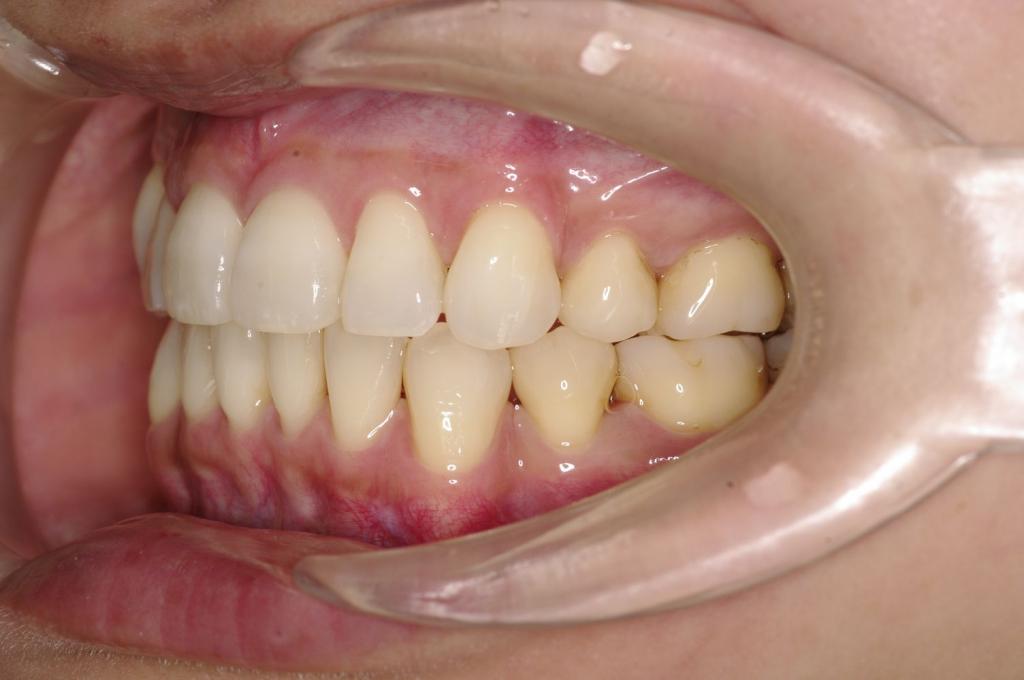

前歯、出っ歯・開咬の矯正治療

(治療期間、治療前後写真、治療方法、費用)WORKS